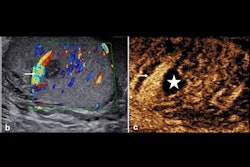

Images show lung ultrasound findings of major pleuro-pulmonary pathologies. (a) Pleural effusion; (b) Pneumonia; (c) Bronchopneumonia; (d) Acute pulmonary edema; (e) Chronic obstructive pulmonary disease exacerbation; (f) Pleuropulmonary tumors; (g) Acute respiratory distress syndrome.Springer